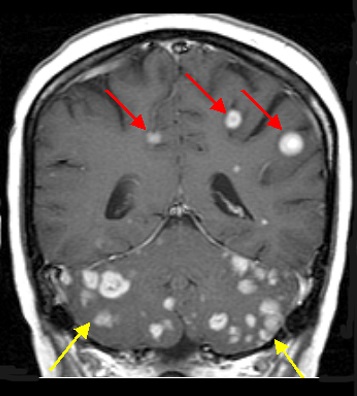

Brain metastases are relatively common in lung cancer, seen in about 15% of cases, and the management of them is evolving as technology and our preferences change. For decades, whole brain radiation therapy (WBRT) was the only game in town and did a reasonable job controlling a problem that we couldn’t manage readily any other way – chemotherapy generally doesn’t penetrate well into the brain, and brain surgery is only a feasible option for one or a few brain metastases, not many.

But over the past 10-15 years, stereotactic radiosurgery (SRS), which is more broadly known by the marketed names Gamma Knife or Cyber Knife, became more readily available and better studied. It has become a standard of care for patients with 1-3 brain metastases, and increasingly offered and used for far more brain metastases, as WBRT became more feared for its potential to cause short- and long-term cognitive problems. While long-term cognitive function was not a significant concern many years ago, when survival was far more limited, it has become a more relevant and dreaded concern as more patients with lung cancer are living well beyond prior benchmarks.

The second trial, known as NCCTG N0574, was actually presented in the ASCO 2015 Plenary Session and addressed the question of whether WBRT provided additional benefit that more than counterbalanced the risks of it in 213 patients, 72% with lung cancer, who also received SRS for 1-3 brain metastases. On this trial, there was also no significant difference in survival between the treatment arms, while cognitive function was worse in patients with WBRT (92% vs. 64% with cognitive decline 3 months later, for SRS alone or with WBRT, respectively). On the other hand, progression with new or enlarging brain metastases was significantly more common with SRS alone at 3 months (25% vs. 6%) and 6 months (35% vs. 12%).